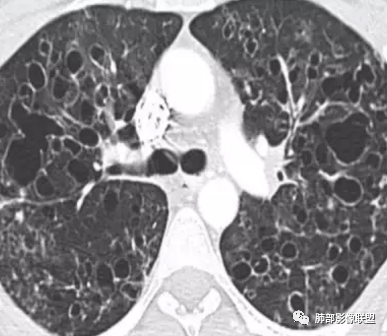

晨读:双肺多发大小不等囊腔影,部分囊有融合,形态不规则,部分壁偏薄,部分囊壁偏厚,囊壁可见结节?血管?右肺上叶及左肺下叶可见条状高密度影,双侧胸膜结节样增厚,临床年轻女性,考虑LAM,鉴别LIP

晨读:女,31,间断咳嗽咳痰9个月,双肺多发大小不等囊泡影,壁薄厚不均,部分囊泡融合成片,双肺另见结节影,边界清晰,考虑PLCH,LAM。

晨读,青年女性,双肺及胸膜下多发大小不等囊腔,大部分呈薄壁,部分囊壁略厚,边缘毛糙,部分囊腔有融合,双肺内散在条状高密度影,考虑LAM

晨读:女,31,间断咳嗽、咳痰9月。卵巢交界性囊腺瘤术后。胸部CT:双肺多发大小不等薄壁囊腔影,部分融合,形态不规则,个别囊壁偏厚。右肺上叶及左肺下叶纤维索条影。左下叶不规则囊腔影,壁不均匀增厚,周围不规则实性成分加GGO,放射性毛刺,胸膜牵拉。考虑:囊腔型Ca?转移?鉴别PLCH,Lam,LIp,BHD,CF,CPAM等,听大咖解析。

胸部CT:两肺多发囊腔,中上肺受累为主,囊腔形态不规则(囊有点丑),分叶状,囊壁厚薄不均,大部分囊壁薄。尚有一些结节影。